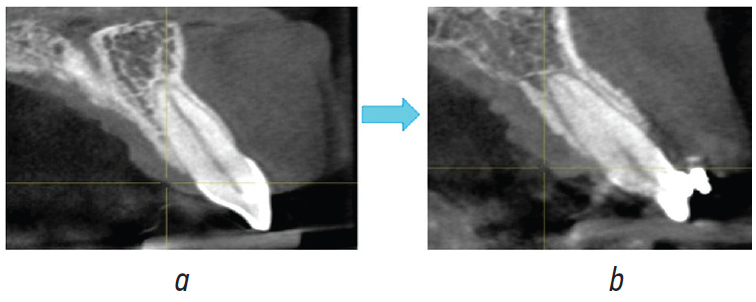

Применение в нашей клинической практике комбинации двойных и одиночных брекетов в рамках одной системы позволило обеспечить качественный контроль ротации, ангуляции и торка зубов на этапах лечения, а значения торка –5° нижних центральных резцов и ангуляции –6° первых нижних моляров, применяемые в Vari-Simplex Discipline, — уменьшить показания для удаления отдельных зубов в процессе ортодонтического лечения при условии наличия костной ткани в переднем отделе зубного ряда по данным КЛКТ [6] (рис. 2). Согласно нашему клиническому опыту, последовательность применяемых дуг может быть незначительно изменена по сравнению с предложенной автором, ввиду развития ортодонтии как области стоматологии в целом, появления дуг из новых материалов, широкого внедрения в ортодонтическую практику анализа костной ткани пародонта и корней зубов при помощи КЛКТ [7–10] (рис. 3). В то же время это не приводит к значительному увеличению количества применяемых дуг за весь период лечения, что соответствует ранее предложенной автором концепции. Увеличенное межбрекетное расстояние дает возможность аккуратно воздействовать на перемещение зубов, а использование стальной дуги сечения .017 × .025'' в качестве завершающей в .018'' пазу — обеспечить бóльший контроль торка по сравнению с брекетами .022'' паза, где в большинстве случаев подразумевается применение стальной дуги сечения .019 × .025'' в качестве завершающей.

Рис. 3. Рентгенологический контроль до (a) и на этапе (b) ортодонтического лечения

Fig. 3. X-ray monitoring before (a) and during (b) orthodontic treatment